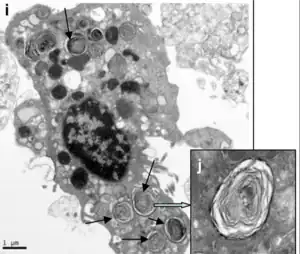

Se les llama también neumocitos granulares o células alveolares granulares (AEC2 en inglés).

Los neumocitos tipo II representan el 60% del total de la población celular del alvéolo, pero ocupan solamente el 10% de la superficie alveolar.[2]

Son de gran importancia por producir el surfactante pulmonar, el cual liberan mediante un mecanismo de exocitosis hacia la luz de los alvéolos.[4]

Se encuentran distribuidos en pequeños grupos entre los neumocitos tipo I. Tienen forma cúbica y poseen microvellosidades en su superficie libre apical. En su interior contienen una serie de vacuolas llamadas citosomas donde almacenan el surfactante pulmonar que secretan al alveolo mediante un proceso de exocitosis. El surfactante pulmonar se mezcla con agua reduciendo su tensión superficial y formando una fina capa que recubre toda la superficie alveolar.